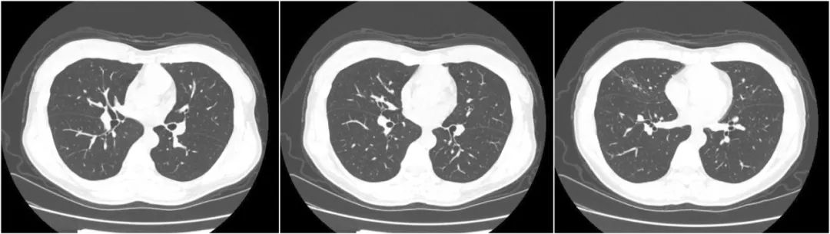

治疗一个半月后患者症状好转无其他不适,复查CT如下。